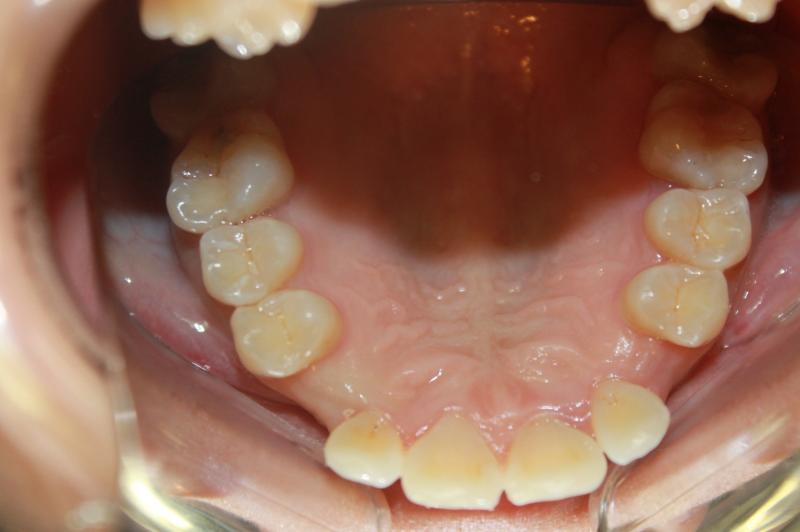

INVISALIGN - 13 months, 1 lower tooth removal, 1 series of aligners to align teeth and create the proper amount of space for 2 cantilever bridge to replace congenitally missing cuspids. COSMETIC DENTISTRY - 2 porcelain cantilever bridges and cosmetic bonding to reshape incisors and close gingival spaces. TOTAL TREATMENT TIME, 15 months

Cosmetic Dentistry, Mid-line Asymetry, Missing Teeth, Severe Crowding